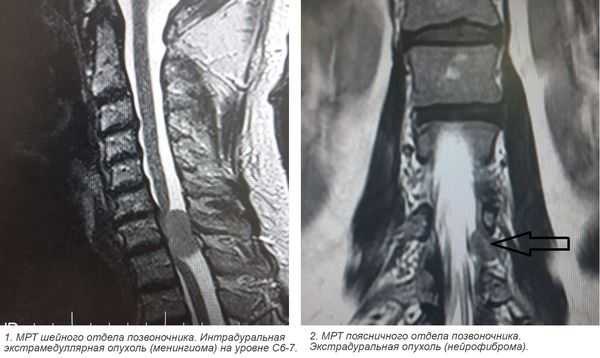

- интрамедуллярные опухоли — формируются из клеток мозгового вещества и растут внутри спинного мозга;

- экстрамедуллярные опухоли могут быть экстрадуральными (располагаются над твёрдой мозговой оболочкой) и интрадуральными, или субдуральными (локализуются под твёрдой мозговой оболочкой).

- менингиома (из клеток оболочек головного и спинного мозга);

- невринома (из клеток, образующих миелиновую оболочку нервов);

3. Магнитно-резонансная томография (МРТ) с контрастным усилением. На данный момент это основной метод диагностики новообразований спинного мозга. МРТ позволяет визуализировать весь спинной мозг и позвоночник и определить локализацию опухоли. Накопление контрастного вещества определяет не только распространение, но и гистологическую структуру опухоли [5] [6] .